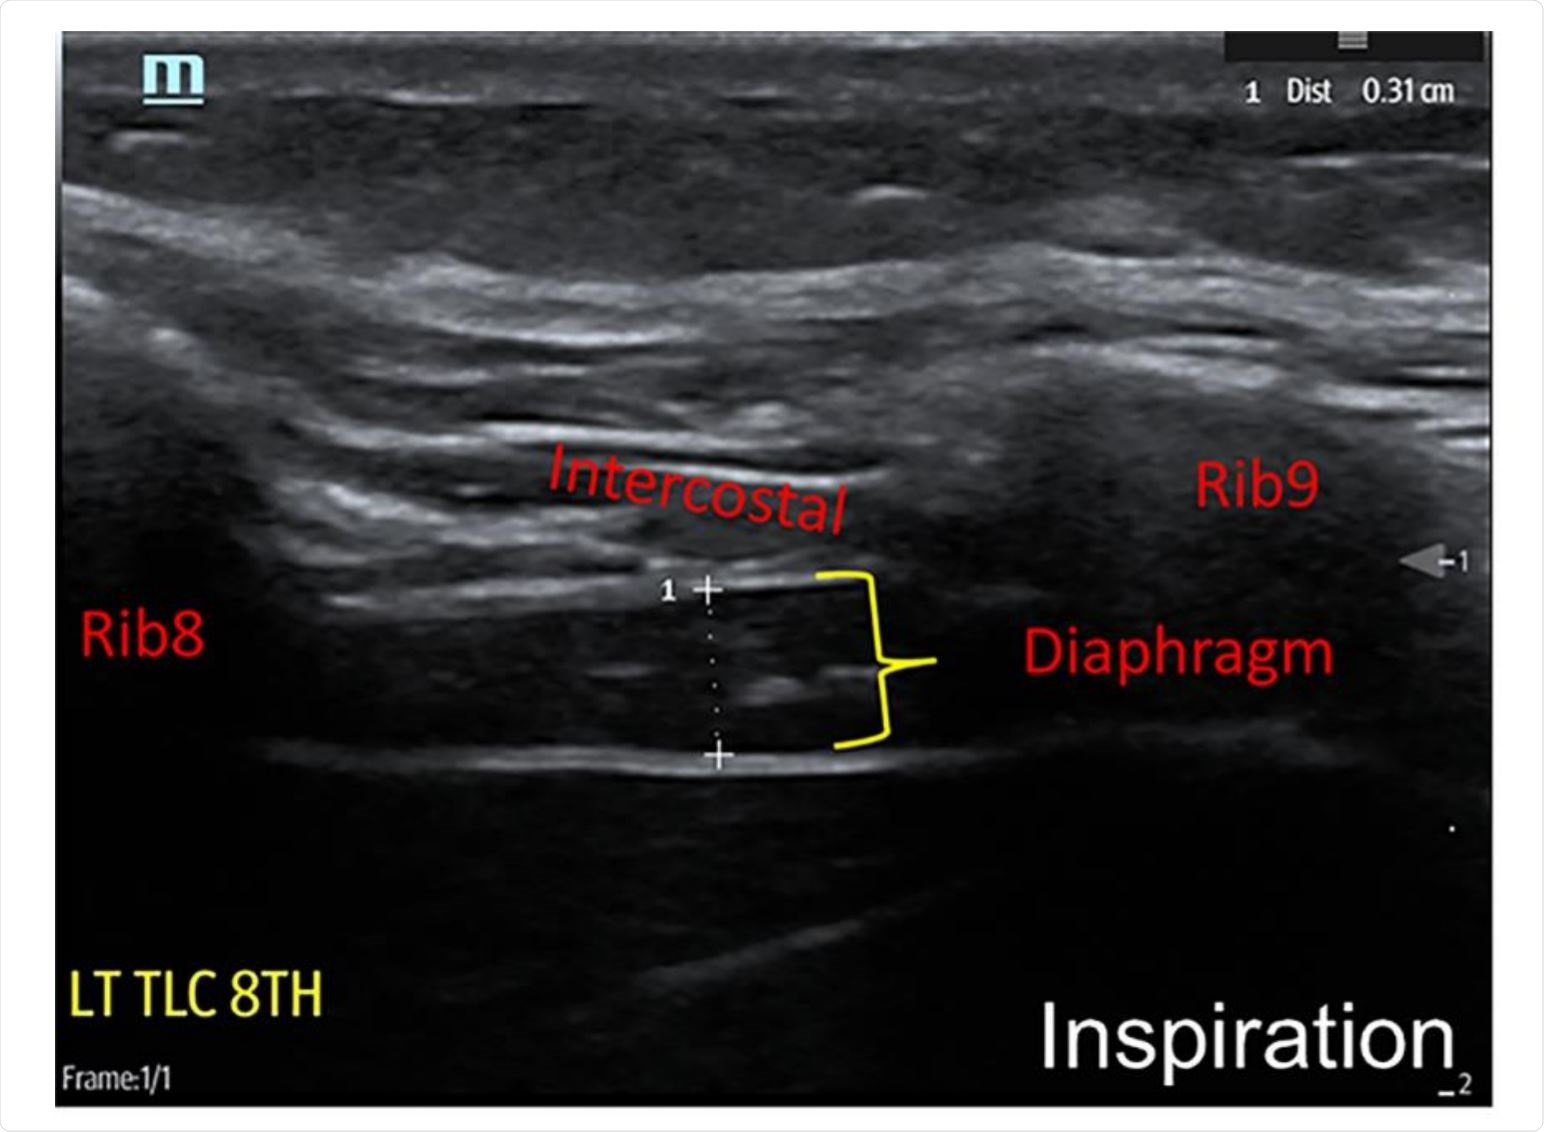

Place one hand on your abdomen and breathe deeply. Reduced number of alveoli air sacs required for normal breathing. In severe cases when there is no simple treatment that can relieve dyspnea your doctor may prescribe morphine. Congenital diaphragmatic hernia CDH. There is usually a long history of heavy smoking. Shortness of breath may be accompanied by wheezing. Diaphragmatic dysfunction caused by transverse myelitis or leukemic infiltration of the cervical spinal cord in a patient with leukemia and shortness of breath. To treat phrenic nerve irritation This condition can be managed with a breathing pacemaker which takes over the responsibility of sending messages to the diaphragm. The cause for shortness of breath was thought primarily due to stable angina on tread mill test positive finding but Chilaiditis syndrome should also be considered as a cause for the shortness of breath.

The rise in intraabdominal pressure further increases intrathoracic and lung volume by pushing the lower rib cage outward. In severe cases when there is no simple treatment that can relieve dyspnea your doctor may prescribe morphine. Diaphragmatic dysfunction caused by transverse myelitis or leukemic infiltration of the cervical spinal cord in a patient with leukemia and shortness of breath. Diaphragmatic plication a surgical procedure that pulls the diaphragm down by introducing a repeated series of continuous sutures across the diaphragm and pulling the muscle taut. A bedside fan or open window with a breeze are also simple but very effective treatments to lessen dyspnea. Depending on the severity of injury to the diaphragm some doctors recommend non-surgical options to treat the breathing issues associated with diaphragm weakness and paralysis. P E Pulmonary embolism.